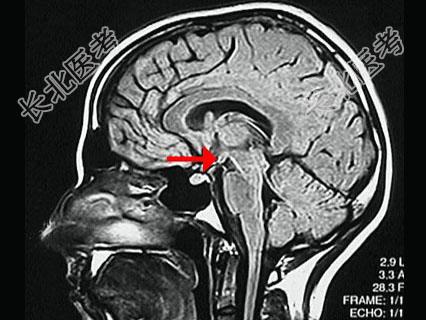

- 单项选择题如图箭头所示为大脑哪个部位 ( )

A、前连合

B、后连合

C、室间孔

D、乳头体

E、垂体